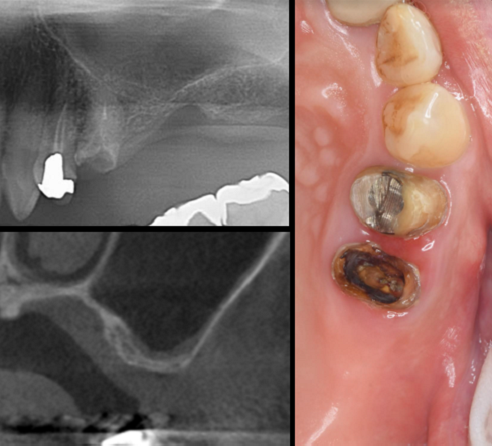

症例1

治療前

治療後

主訴 左上小臼歯から大臼歯部にかけて、脱離・歯冠崩壊、及び欠損があり、左奥では物が噛めない。

まだ年齢も50代と若く、義歯は煩わしく嫌であるという訴えがあり、左上5番・6番にインプラントを2本埋入する計画を立案。

副鼻腔までの距離がわずかしかないので、ソケットリフトと、骨の緻密化を計る為に、C・C・Wドリリング法を併用。

オぺから仮歯装着まで3ヶ月を要し、4ヶ月未満の治療期間を経て最終補綴物ジルコニア2本を装着。

リスクとしては、ソケットリフト(骨造成)による一過性の副鼻腔炎が起きる可能性がある。まれに洞底膜が破れる可能性がある。

ただし、膜は約3週で再生するので、膜の回復を待ち、再オペを行う。

費用 116万(オペ・ソケットリフト・人工骨・採血による濃縮血小板生成・仮歯・最終補綴物まで含む)